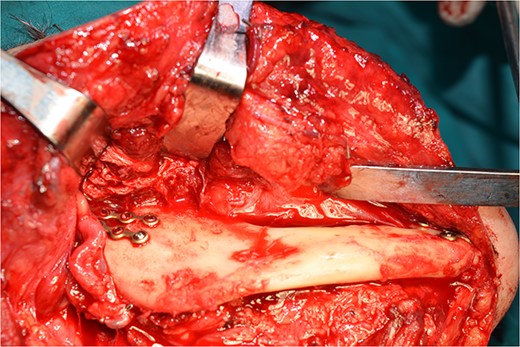

Operatively, after induction to general anaesthesia via orotracheal intubation, an extended submandibular incision to the right of the neck was performed and the mandible was revealed. The marginal branch of the facial nerve was recognized and protected. Following this, the double osteotomy of the mandible was performed in the parasymphysis—with preplating of two miniplates with four holes—and in the subcondylar area—with preplating of two miniplates with four holes (Figs 3 and 4). The mandibular ‘swing’ that was performed straight after that (Fig. 5) gave space for the dissection of the CCA and the bifurcation. All the branches were prepared, and the aneurysm was accessed (Fig. 6). The reconstruction was achieved by bypassing the aneurysm, trans-positioning of the right ECA and end-to-end anastomosis of the ECA with the healthy peripheral end of the ICA near the skull base, after the lignification of the peripheral end of the ECA and its smaller branches (Fig. 7). The anastomoses were checked for leakage (Fig. 8), the mandible was reduced and the easily fixated rigidly after preplating (Fig. 9).

All the branches of the carotid artery are demonstrated prepared, and the aneurysm is demonstrated.